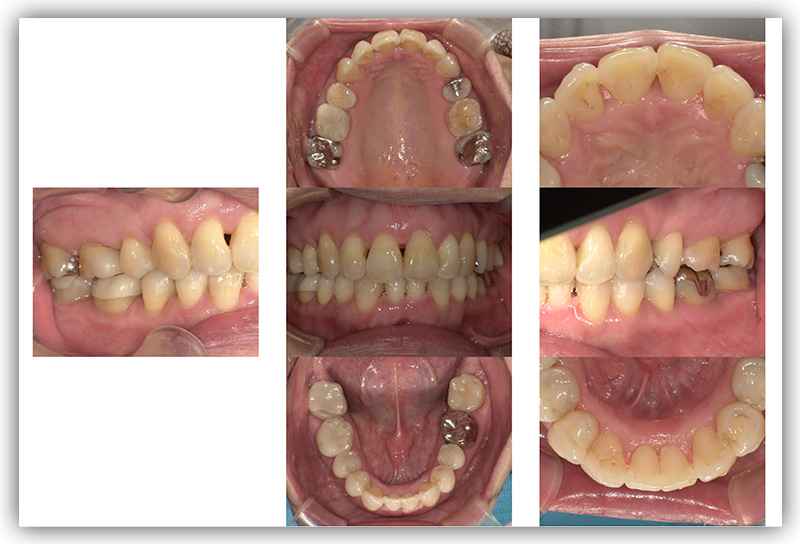

CASE_01

40代男性(インビザライン矯正+セラミック治療)

- 患者さん情報(年齢・性別)

- 40代 男性

- 主訴

- 歯並び、銀歯を白くしたい

- 治療箇所

- 10か所

- 治療方法

- 銀歯をセラミックに変更

- 費用

- インビザライン77万円

- セラミック10か所約80万円

- 治療期間

- インビザライン約1年

- セラミック治療10か所約8か月

- その治療によるリスク・副作用

- 歯肉退縮することがある

- 矯正中はしみたり、痛みを伴うことがある